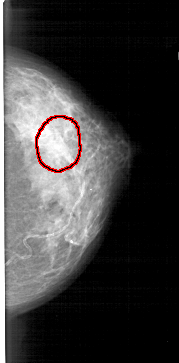

A_1447_1.LEFT_CC

LEFT_CC LINES 5101 PIXELS_PER_LINE 2806 BITS_PER_PIXEL 12 RESOLUTION 43.5 NON_OVERLAY

FILE: A_1447_1.RIGHT_CC.OVERLAY

TOTAL_ABNORMALITIES 1

ABNORMALITY 1

LESION_TYPE MASS SHAPE LOBULATED MARGINS OBSCURED

ASSESSMENT 3

SUBTLETY 1

PATHOLOGY BENIGN

TOTAL_OUTLINES 1

BOUNDARY